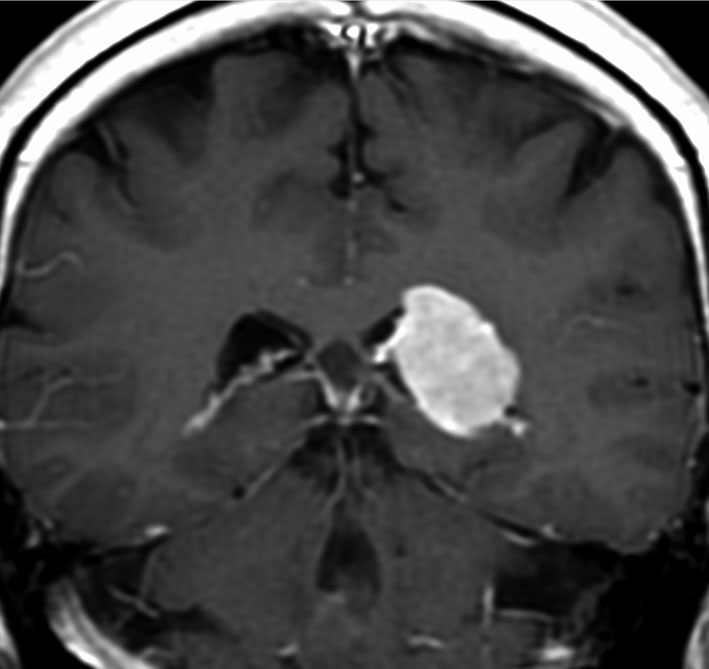

上矢状洞髄膜腫 superior sagittal sinus meningioma

また別な例です。1986年13歳の時に2度の開頭手術を受けましたが,全摘出できずにそのまま経過観察されました。

左の画像は1997年の術前のものです。これを2回に分けて全摘出しました。上矢状洞はやはり冠状縫合のあたりから静脈洞交会まで摘出しました。その下の大脳鎌も全て摘出したので,直静脈洞の上壁を開けることになり,直静脈洞からの激しい出血があり縫合して直静脈洞形成をするのが大変でした。手術後16年が経過しますが再発していませんし,社会人として普通に暮らせています。

この例が教えてくれることは,上矢状静脈洞は全長にわたり切除してしまっても,神経脱落症状を出さないで普通に生きて行かれるということです。